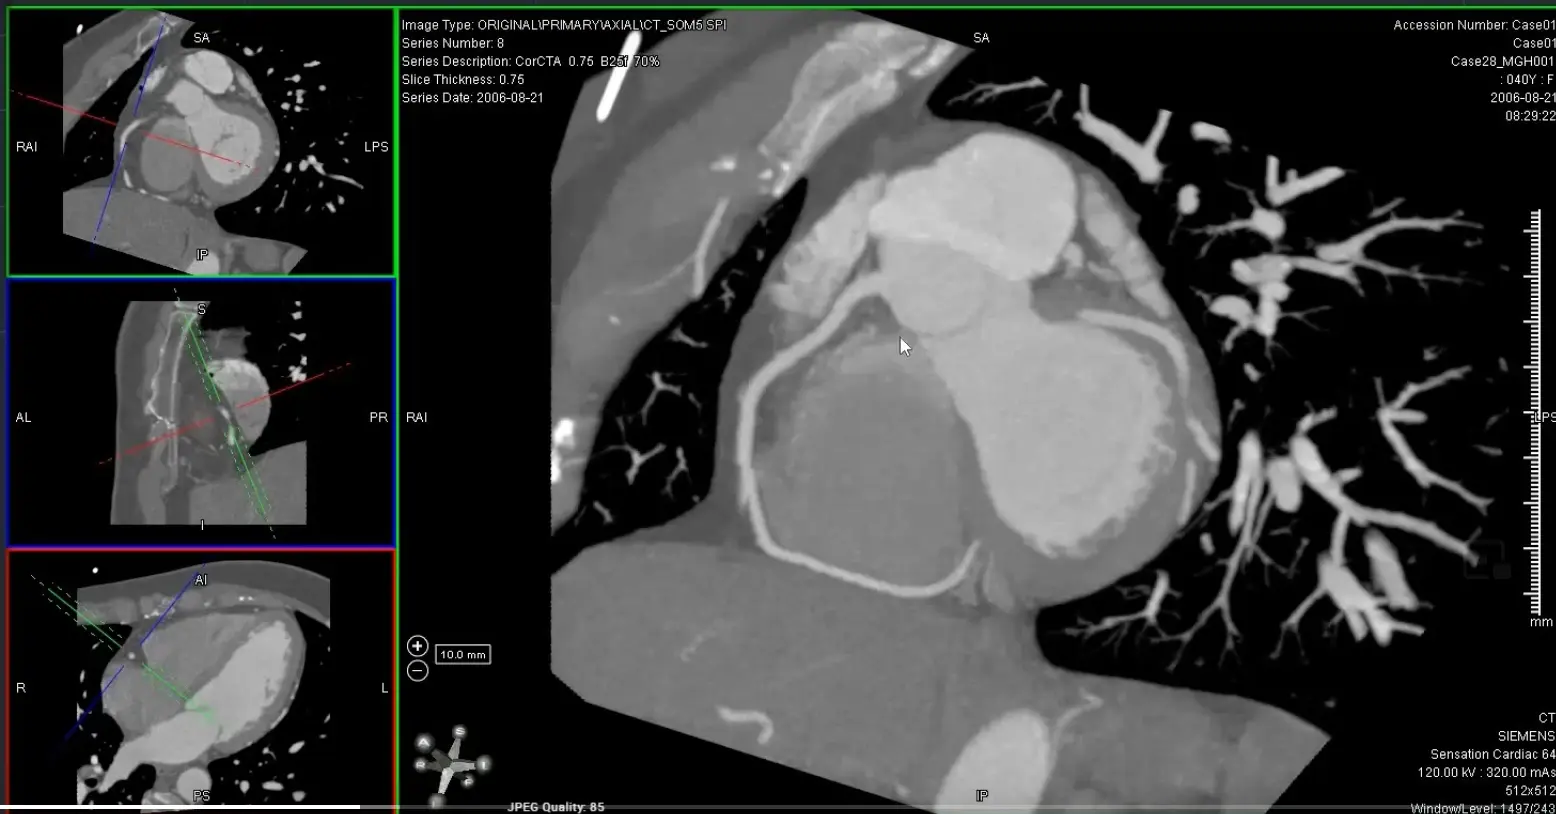

’C’ view of RCA

Useful to view RCA and LCx

Both the RCA and LCx lie along the atrioventricular groove, so the ‘C’ view is useful to evaluate the RCA and LCx. When you get your RCA lined up (as below) in the MIP projection, you can scroll along and assess the LCx as well.

- Coronal view: Position crosshair (⌖) at mid-RCA

- Axial view: center on the SAX view of the RCA

- rotate ⌖ in the axial view until you are aligned parallel to the ventricular septum on your coronal window

- In your axial view, rotate ⌖ to align the orthogonal view (e.g. coronal window) so that the orthogonal view is along the atrioventricular groove

- Switch to MIP view

- MIP will help give you an overview of the vessel. Once you identify some areas of concern → switch to thin-slice images for closer investigation 🔍 and evaluation for stenosis.

- Go down to the thinnest possible section within the MIP view

Avoid assessing diameter stenosis using thick-slab MIP

When quantifying stenosis, you will always want to use thin slice images.

MPR of ‘C’ view of RCA

Above, but changed to MIP